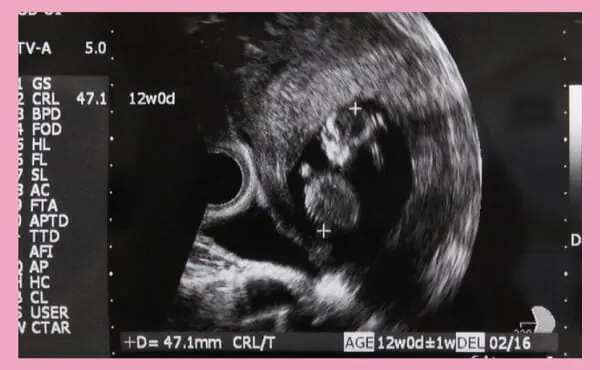

妊娠12週頃の赤ちゃんの平均的な大きさは、赤ちゃんの大きさを示す数値であるCRL(Crown-rump length)で、約5〜6cmです。

CRLとは、胎児の頭の先からお尻までの長さを測定したものになります。

果物で例えると、みかんくらいの大きさです。

体重は約40〜50gになり、卵1つ分くらいの重さになります。